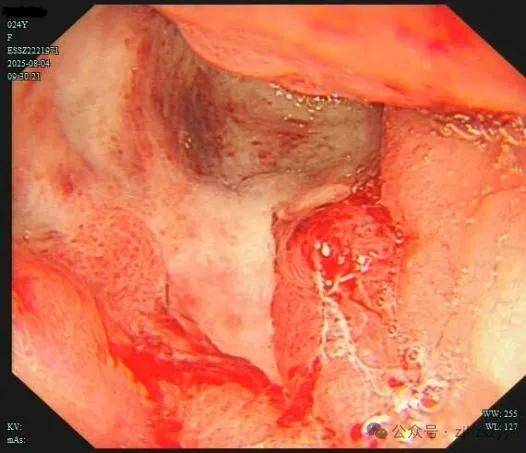

今年24岁的小雯(化名),长得清秀漂亮,从小就对表演充满热情,常常对着镜子模仿电视剧中的角色。上大学后,她利用课余时间兼职拍广告、客串MV,积累了不少经验,毕业...